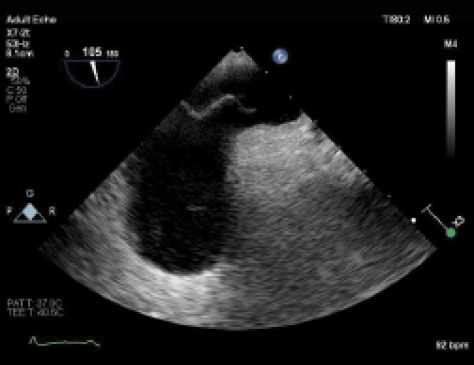

Figure 1. PFO with atrial septal aneurysm. There is wide opening of the septum primum, much larger than is usually seen with most PFOs.

Now, 2 years later, the patient wishes to start a family and is reconsidering her aspirin therapy. No additional events have been reported since the patient has been off contraceptives. TEE was performed again and showed a large PFO with atrial septal aneurysm (Figure 1) and large right-to-left shunt (Figure 2). Treatment proceeded with implantation of a 35-mm Amplatzer PFO occluder (Abbott Vascular) without any complications (Figure 3).